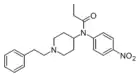

p-Nitrofentanyl [35] | N-(4-Nitrophenyl)-N-[1-(2-phenylethyl)-4-piperidinyl]-propanamide | |

|